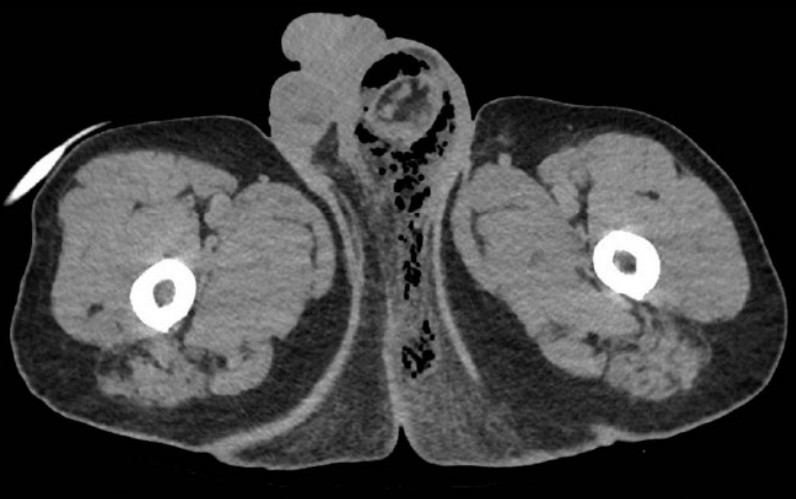

You are asked to review an unwell 64-year-old male in your emergency department. A quick review of previous …